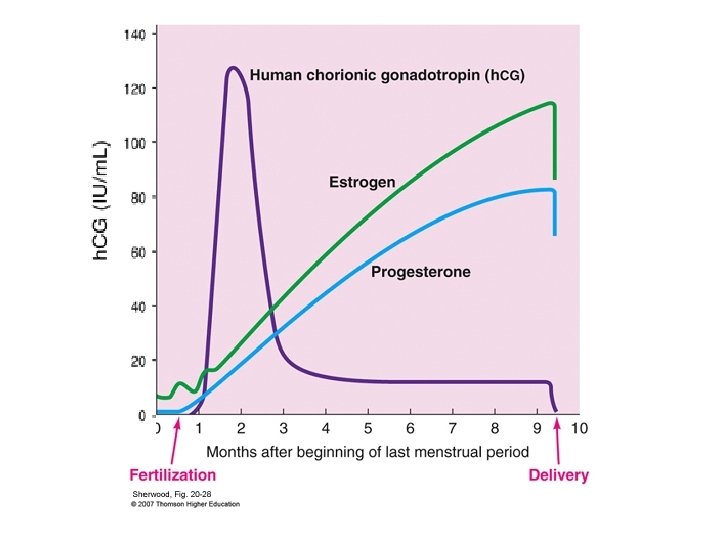

Cunningham et al, Williams Obstetrics, 23 ed , 2010

At the 9 week follow up the β h. CG level : 2 u/L Is this level sufficient to stop follow up ? No 4 - The Scenario case Cunningham et al, Williams Obstetrics, 23 ed , 2010